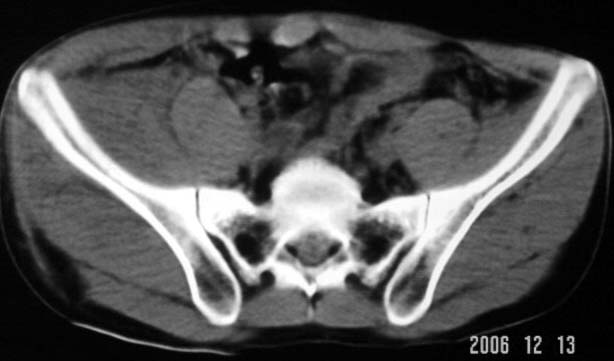

以下是引用守望可可西里在2006-12-13 22:25:00的发言:[br]再明确不过的右侧髂骨骨折,呵呵,这回总不会被忽悠了!

以下是引用liuyue在2006-12-13 23:45:00的发言:[br]右侧髂骨骨折伴局部软组织及腹壁肿胀

以下是引用xiaoniu在2006-12-13 22:22:00的发言:[br]右侧髂前上嵴骨折伴局部腹壁血肿。[br][br][本贴已被 xiaoniu 于 2006-12-13 22:24:13 修改过]